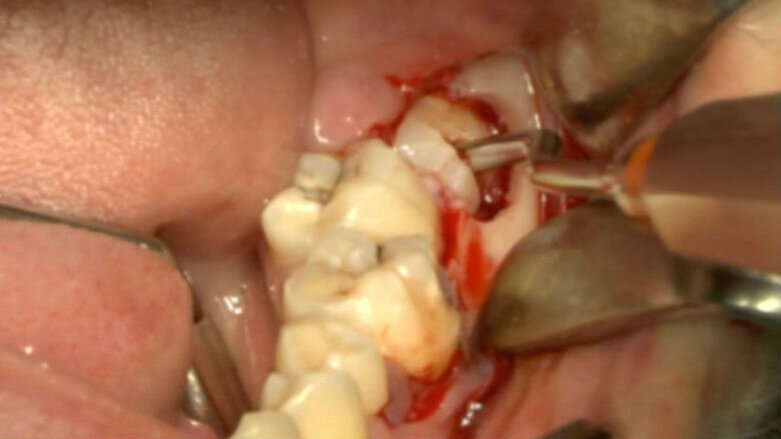

Fig. 7_Ostectomia completata.

Fig. 8_Odontotomia. Il taglio si trova fra la zona di massima circonferenza e la giunzione smalto cemento.

Fig. 9_Frattura della corona sezionata mediante leva dritta.